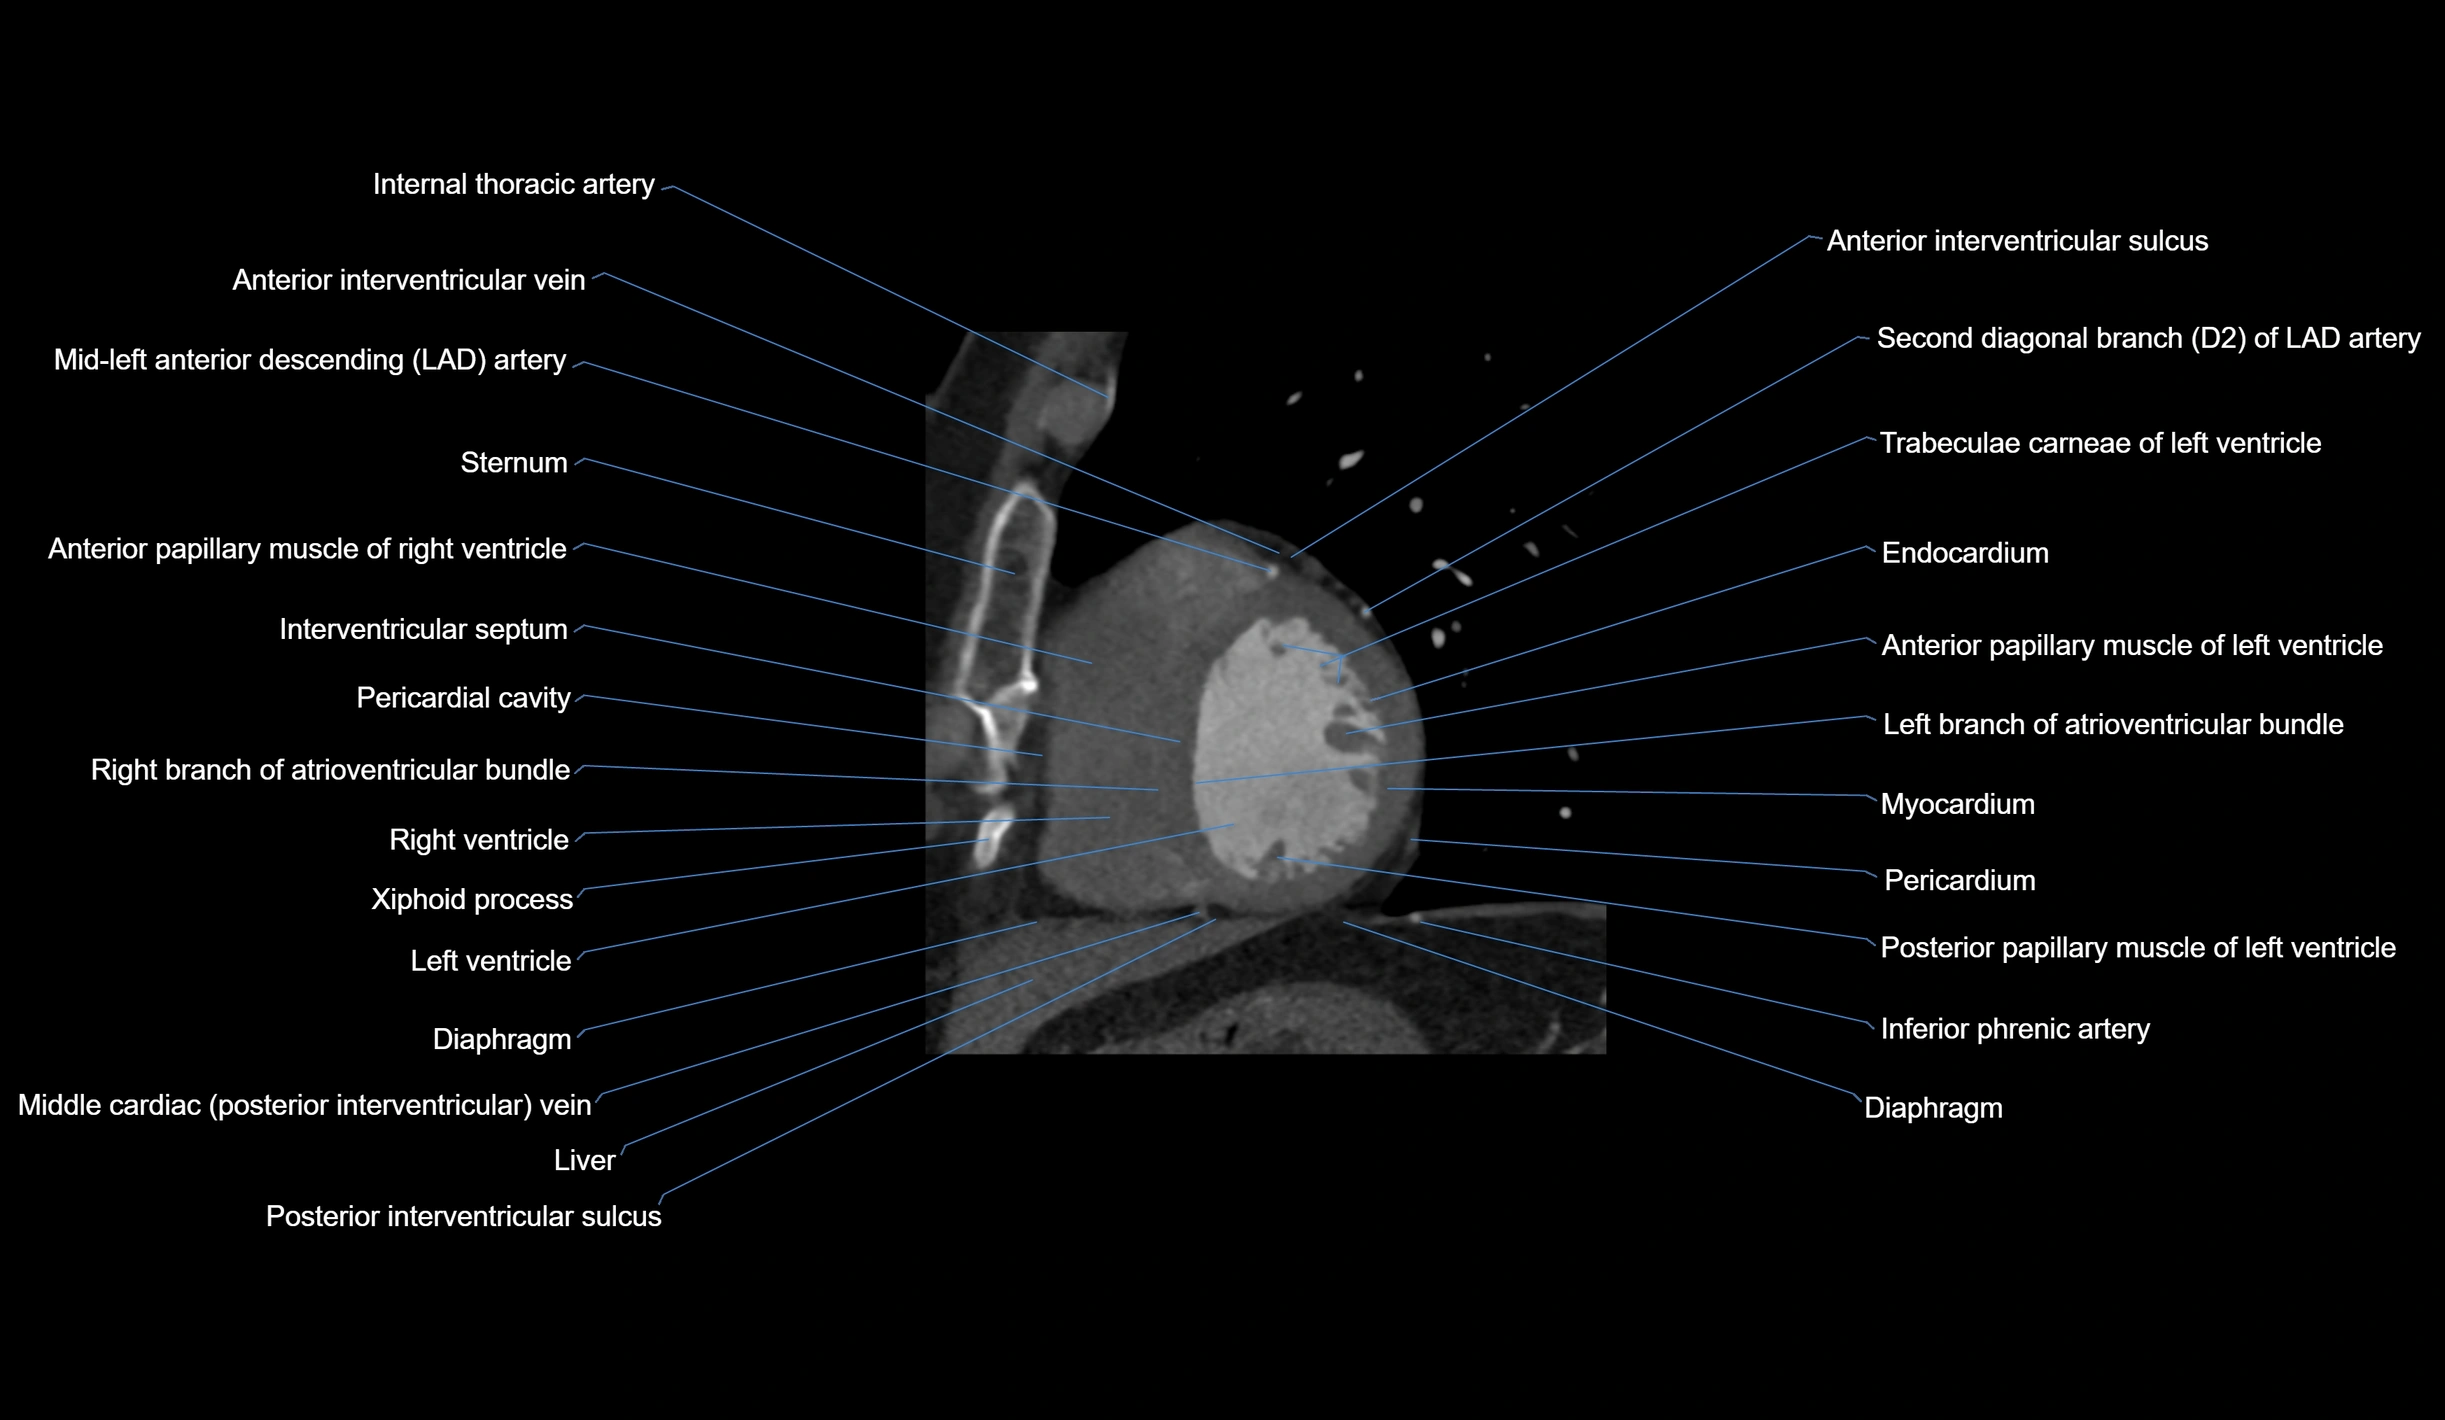

- Anterior interventricular sulcus

- Costal cartilages

- Distal left anterior descending artery (dLAD)

- Endocardium

- Inferior phrenic artery

- Interventricular Septum

- Left branch of atrioventricular bundle

- Left ventricle

- Middle cardiac vein

- Myocardium

- Pericardial cavity

- Pericardium

- Posterior interventricular sulcus

- Posterior papillary muscle

- Right branch of atrioventricular bundle

- Right ventricle

- Second diagonal branch (D2) of LAD

- Sternum

- Trabeculae carneae

- Xiphoid process of sternum